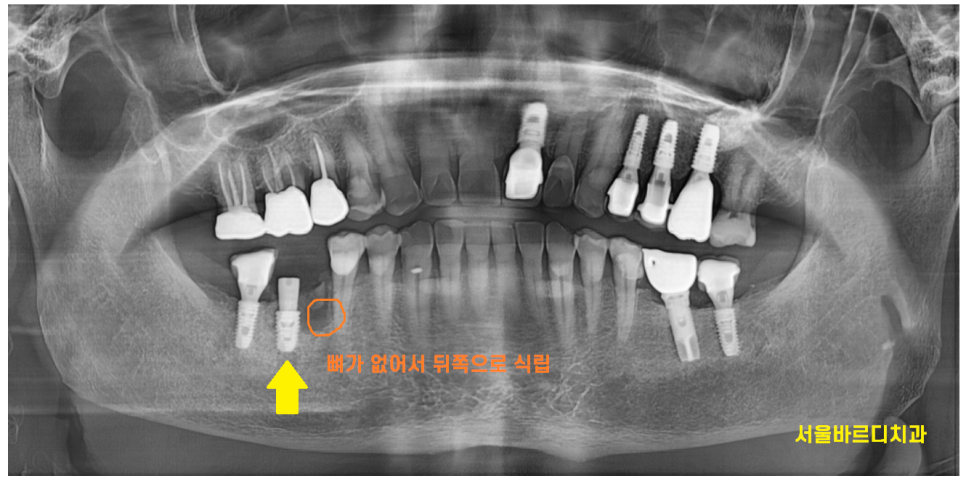

24.01.26

엑스레이 찍은 사진을 보고

한눈에 보기에도 으스러진 치아들 ㅠㅠ

치아 뿌리 균열 상태에 비하여

뼈는 나쁘지 않아서

(천만다행이죠~?)

뽑고 암사동 치과에서 임플란트 바로 식립해드렸습니다.

ct에서 분석 했을 때

뼈가 좀 모자란 부분이 있어서

뼈이식도 함께 시행했는데요.

치아 뿌리 균열이 하루 이틀 있던 일이 아니라

잇몸뼈가 부분적으로 녹은 부분이 있었습니다.

잇몸 앞쪽으로 뼈가 없다보니

임플란트 위치를 뼈가 많은 뒤쪽으로 심어드렸습니다.